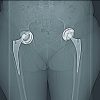

Outpatient clinical control was carried out in an average time of 2 years (8 months–4 years), beginning at 2, 4, and 8 weeks after surgery. The patients present complete resolution of pain; surgical wounds were completely healed without local signs of infection. Femur radiographs showed the implant in adequate position, without any sign of loosening or failure. However, one of the patients (history of firearm injury) required the removal of the osteosynthesis material due to the persistence of the bone infectious process 1 year after the surgical procedure.

Retrograde cementing technique was performed, which is widely known since Barrack et al. proved in 1992 that it decreases the loosening rate significantly [8]. Recently, in 2019, Phelon et al. reported that cemented femoral endoprosthesis is a versatile option that allows immediate full weight-bearing. Augmenting the construct with a condylar plate fixed with periprosthetic screws and surgical cables is an option that ensures more rigidity in primary stability. Literature shows its use, especially in distal femur periprosthetic fractures [9]. Song et al. reported that fixation of periprosthetic fractures with locking plates provided satisfactory results with a low risk of complications and additional surgeries [10]. In addition, a cement mantle was built between the endoprosthesis to achieve an adequate interface between the endoprosthesis and the plate and avoid metallosis or corrosion between the different metals. Using the following keywords, a literature search was performed on PUBMED and EMBASE: Proximal femur endoprosthesis, aseptic loosening, Augmentation, condylar plate, polymethylmethacrylate. We found no articles reporting this technique in aseptic loosening of proximal femur endoprosthesis. Different therapeutic options have been studied for endoprosthesis aseptic loosening including the use of bone allografts, especially for large femoral bony defects [11], use of wire mesh and cerclage wiring with impaction bone allograft into which the femoral stem is implanted [12], and total femur prosthesis, which provides good functional results but high rates of complications such as infection (13–18%), dislocation (6–10%), and material failure (3–6%) [13,14]. In the case of periprosthetic infection, the approach must ensure infection control in the first instance to ensure better results. The revision could be performed in one or two stages with reinfection rates of up to 37% [15]. The clinical relevance of our technique is that it allows early mobilization and weight-bearing, allowing rapid rehabilitation and return to the previous functionality. Our series of patients shows good clinical results on the immediate post-operative period, 2 weeks and 2 months and 4 years follow-up, especially with complete resolution of thigh pain and no radiological signs of development of new loosening of the endoprosthesis (Fig. 4 and 5).